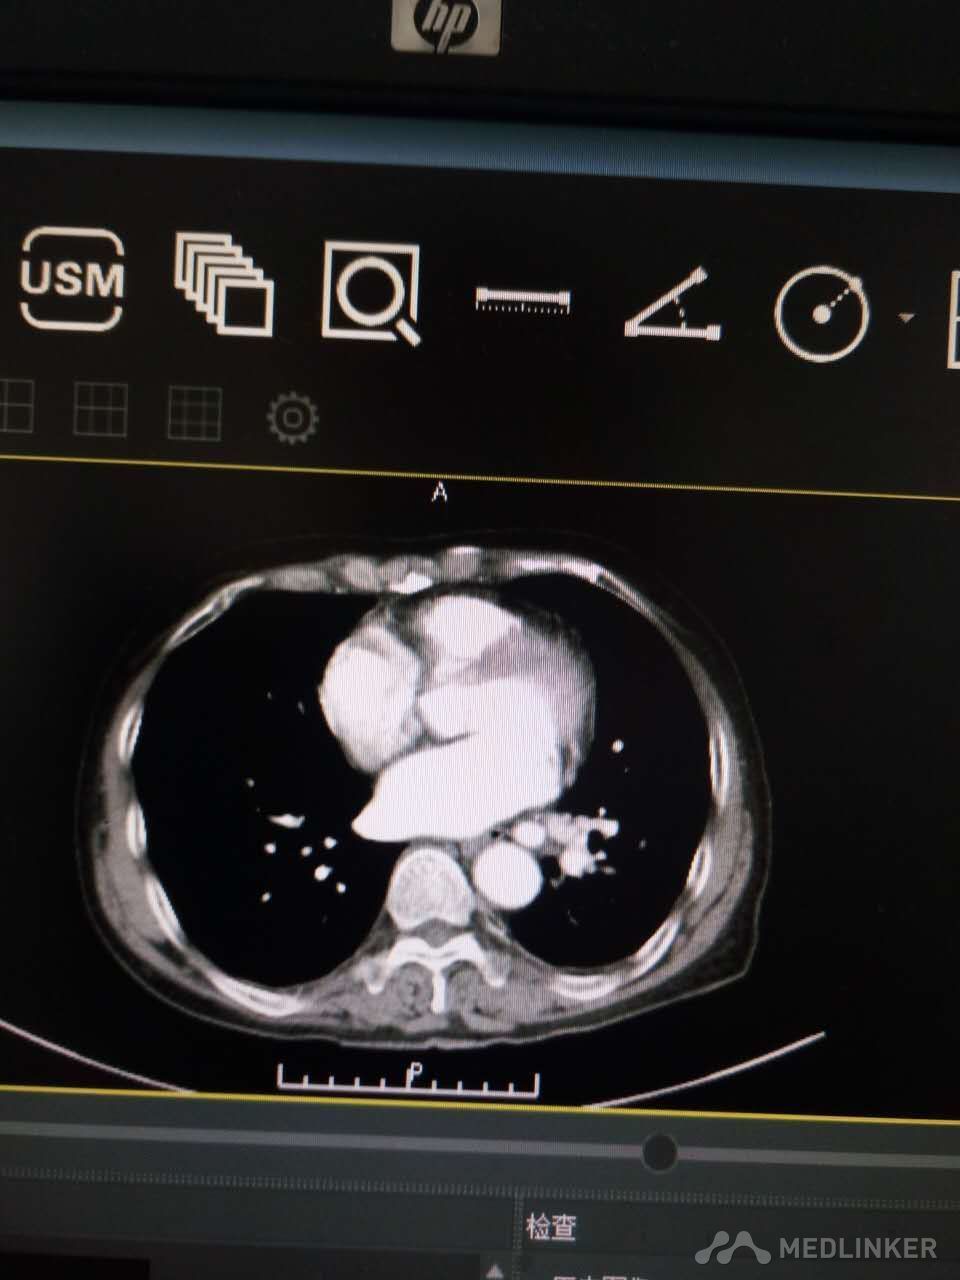

肺血管畸形一例

血管痉挛